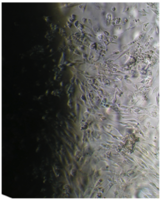

Исследование проведено на первичных культурах дермальных фибробластов и мезенхимальных стромальных клетках человека 4-12 пассажа.

Культуру дермальных фибробластов получали из кожно-мышечной ткани, а культуру мезенхимальных стромальных клеток – из фрагментов крыши черепа абортусов сроком 6-10 недель методом первичных эксплантатов (рис. 1, 2).

Клетки культивировали в стандартных условиях в термостате Sanyo – Incubator MIR-262 при температуре 37°С в среде МЕМ с 10% эмбриональной телячьей сыворотки в пластиковых культуральных флаконах Orange Scientific (производство Бельгии), Corning (производство США) площадью 25 и 75 кв. см. Тестирование производили в культуральных чашках Петри Sarstedt диаметром 3 см (рис. 3).

Вид монослоя и структура клеток не отличались от обычных в течение всех четырех суток наблюдения (рис. 32).

Цитоплазма представлялась гомогенной (рис. 33). Большинство клеток имели одно центрально расположенное ядро правильной округлой формы с 1 или 2 ядрышками.